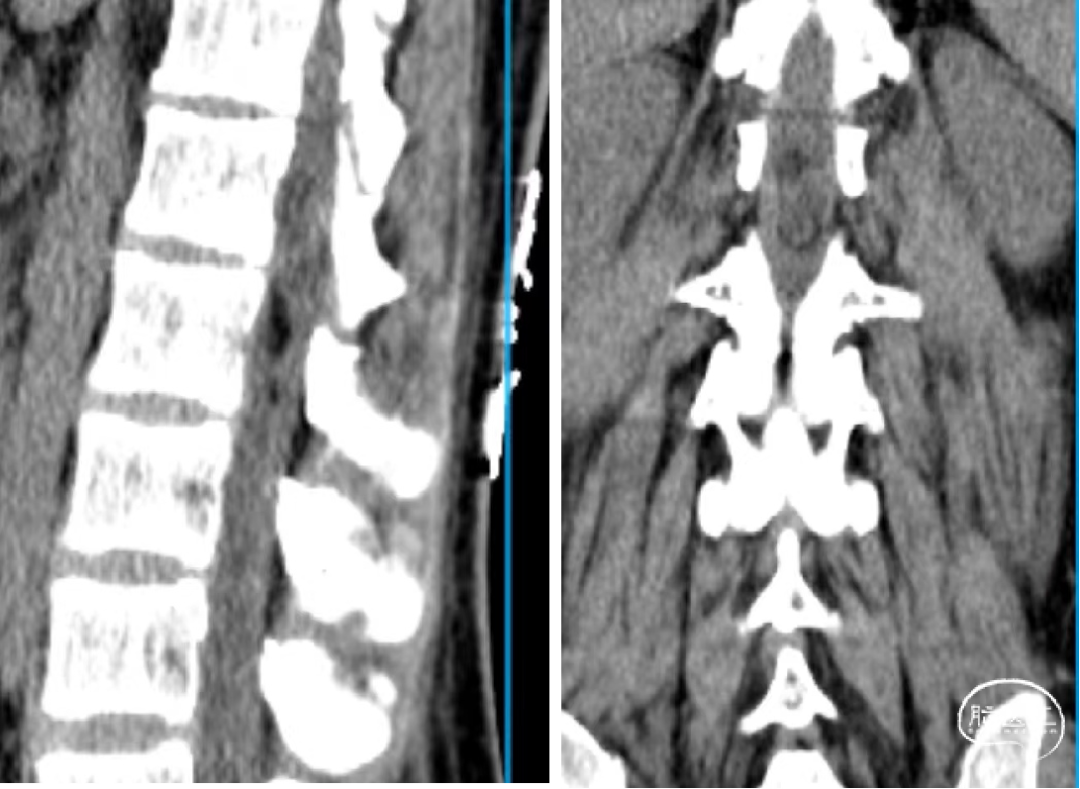

辅助检查:腰椎CT和MR示:L1-2椎管内硬膜下见一软组织信号结节,大小约24mm×12mm×10mm,T1W1低信号,T2W1稍高信号,增强扫描明显强化,但欠均匀,临近脊髓受压改变等。

术前腰椎CT和MR如下: